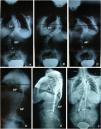

Se intervino a todos los sujetos mediante una artrodesis instrumentada posterior híbrida con tornillos pediculares distales y ganchos proximales (figs. 1 y 2). El sistema de instrumentación empleado fue el Moss Miami® (DePuy) en 13 sujetos y el Monarch® (DePuy) en otros 13 sujetos. En primer lugar, se insertaron los tornillos pediculares en la zona lumbar o torácica baja tras localizar las referencias anatómicas adecuadas1,20–22; se realizaron comprobaciones mediante fluoroscopia intraoperatoria. A continuación, se labraron los lechos para los ganchos de la parte cóncava: habitualmente se comenzó por la concavidad de la curva mayor (por lo general, la curva torácica) en la vértebra estable superior a la vértebra límite superior y 2 vértebras más abajo se aplicaron 2 ganchos pediculares orientados hacia la vértebra proximal; un tercer gancho se insertó hacia la vértebra distal en el ápex o en la vértebra inferior a ésta. Seguidamente, la barra de la concavidad se colocó premodelada según las curvas fisiológicas de cifosis torácica y lordosis lumbar realizando distracción en los distintos segmentos patológicos y, según los casos, con maniobras de desrotación y torsión in situ de la barra en busca de una óptima corrección de la deformidad. Como siguiente paso se implantaron los ganchos de la parte convexa: habitualmente se cerraba el sistema con un gancho (laminar o transverso) orientado hacia la vértebra distal en la vértebra estable superior a la límite superior y otro gancho hacia la vértebra proximal en la vértebra inmediatamente inferior, se insertaba un tercer gancho hacia la vértebra distal en la vértebra ápex y seguidamente se realizaban maniobras de compresión de la curva tras colocar la barra (también premodelada de manera fisiológica).

Evolución radiográfica del sujeto de escoliosis doble mayor (escoliosis de tipo iii de Lenke) en una joven de 14 años. Se indican los respectivos ángulos de las curvas según Cobb y las vértebras limitantes. A) Radiografía anteroposterior prequirúrgica. B y C) Radiografía anteroposterior en inclinación lateral. Se observa una corrección de 10° (13,3%) en la curva torácica y de 18° (28%) en la curva lumbar. D) Radiografía lateral en la que se observan una hiperlordosis lumbar y normocifosis. E) Radiografía lateral 60 meses después de la intervención, con descenso de 8° de la cifosis torácica y de la lordosis lumbar hasta 50°. F) Radiografía anteroposterior 60 meses después de la intervención. Corrección final a los 60 meses del 46,7% en la curva torácica y del 68,7% en la curva lumbar. Se observan una buena alineación axial y signos de fusión sólida.